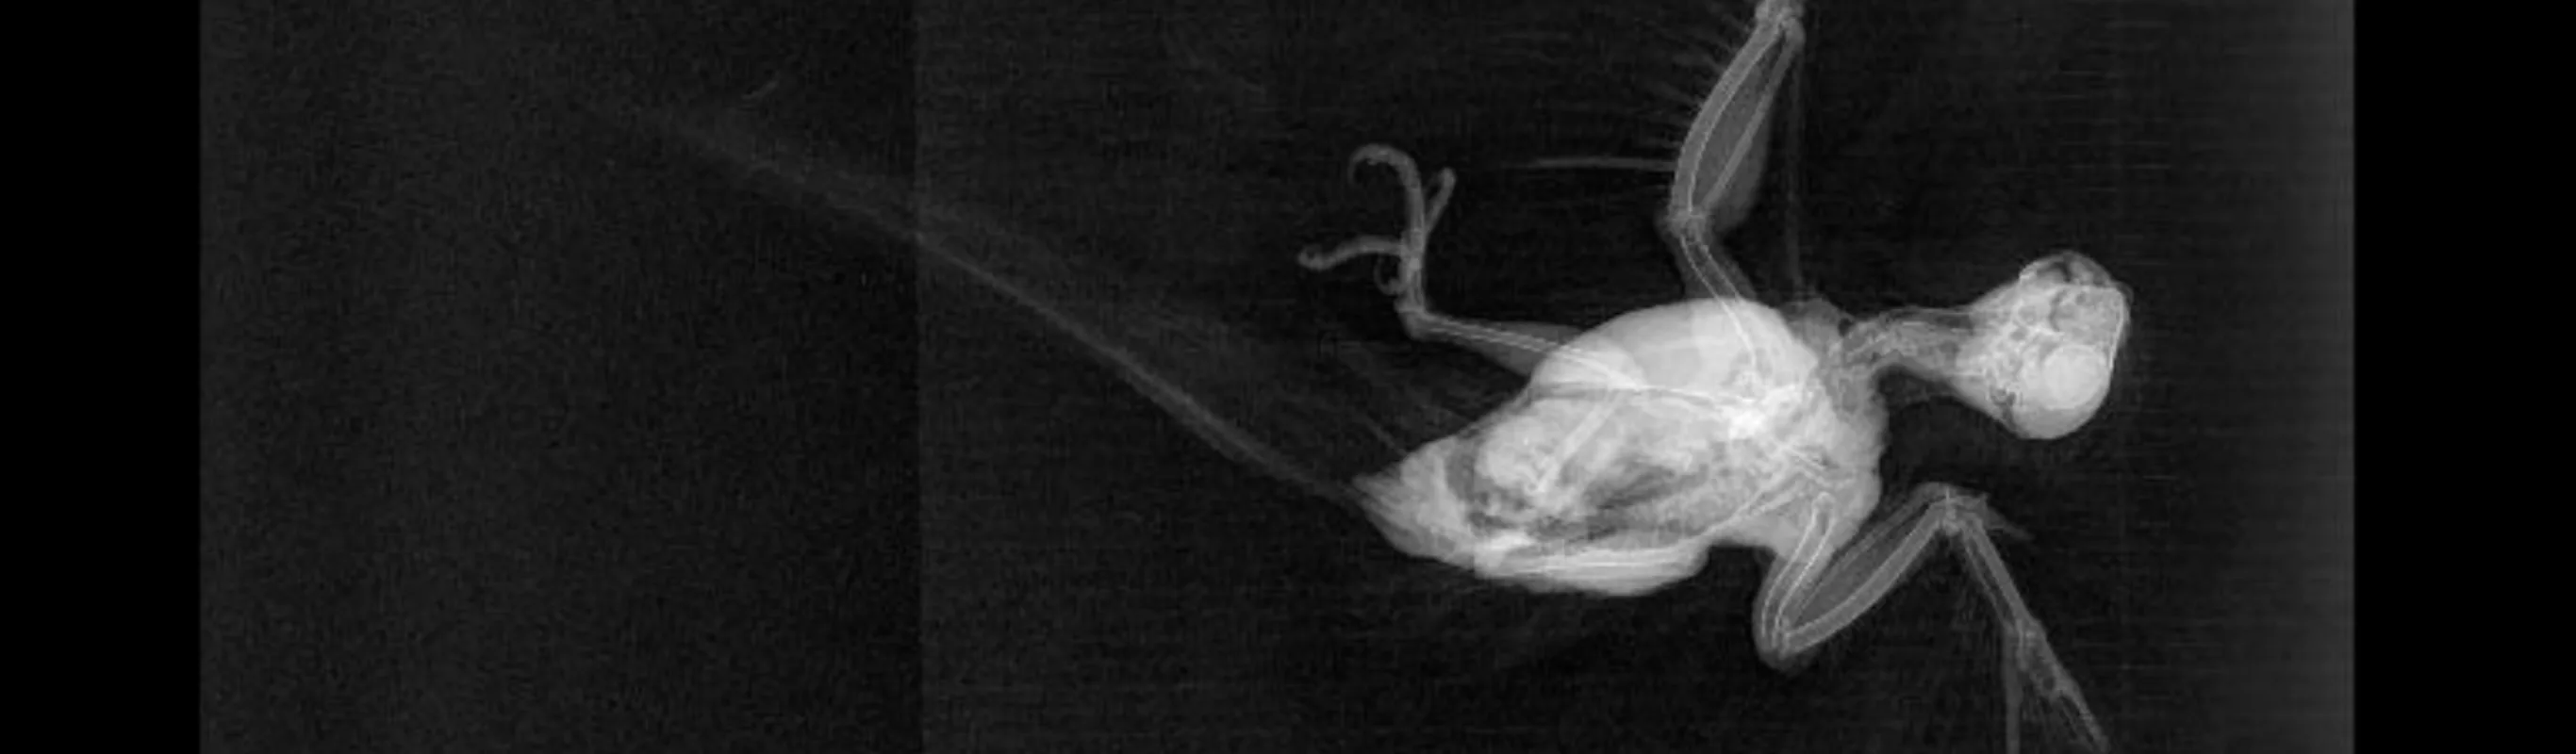

Pet X-Rays (radiographs, xrays or rads) are not just for broken bones! They can give us a look at the stomach, intestines, lungs, heart, liver, spleen and bladder. The veterinarians at Martensville Veterinary Hospital use radiographs to diagnose a problem (an object stuck in the neck or stomach, bladder stones or heart failure for example) and to follow up on patients, like orthopedic surgeries and patients being managed for heart failure. In our senior dogs and cats, we take x-rays to assess the spine, look for evidence of hip, elbow or knee arthritis, and assess the heart and lungs. This helps us develop a more thorough preventative wellness plan and tailor our general anesthetic protocols to be more specific to your pet. Radiographs can also help determine how serious a known problem is (has a cancer spread to the lungs) or help guide the treatment plan (if the foreign body in the intestines isn’t moving we may need to do surgery). Although x-rays are quick and painless, we usually suggest some sedation to keep your pet calm and allow us to get detailed shots at the right angles without squirming or unnecessary pain.Radiographs can be straightforward. But often interpretation of veterinary x-rays requires great skill on the part of the veterinarian. In complicated cases, or for a second opinion we can send our digital images to a board certified veterinary radiologist for interpretation. Because the images are so clear, and they can be sent directly from our clinic in Martensville over a secured internet site to a veterinary referral center, we can even get emergency interpretations back in about one hour!